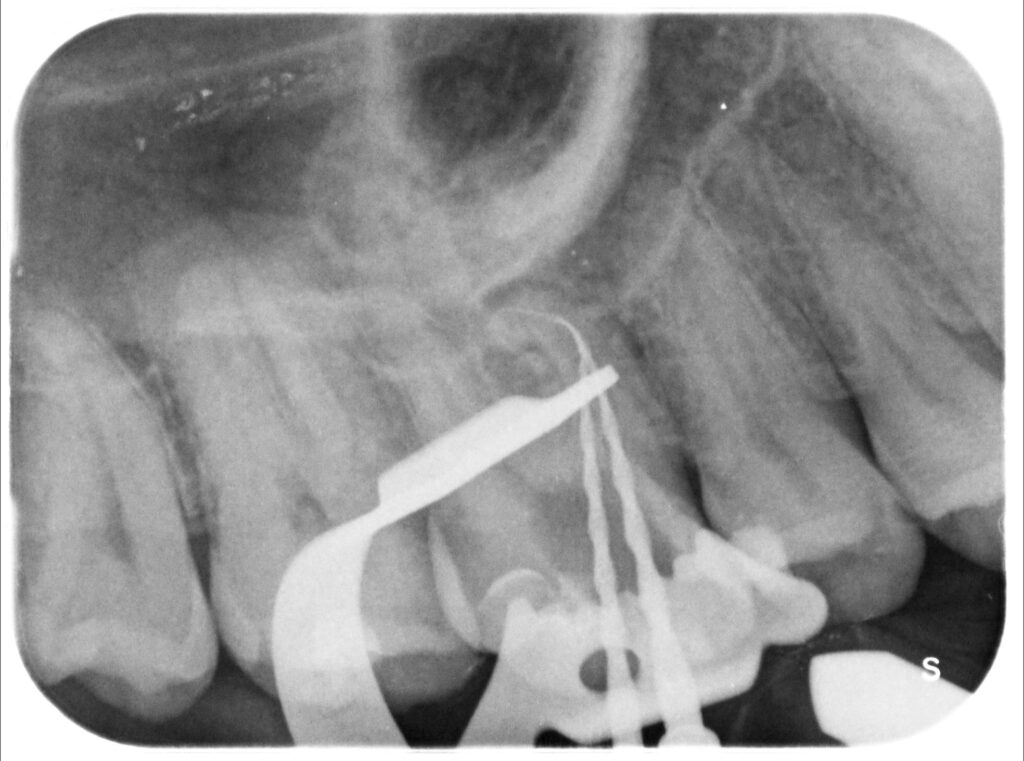

Caso clinico – trattamento ortogrado 1° molare superiore con lesione